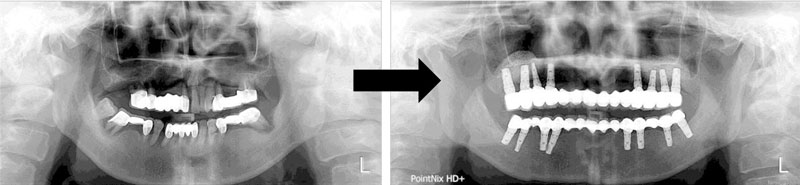

7. 有關於由德國某公司發展出來的 All-on-4 系統在推波助瀾下很對想省錢的病人胃口,往後站在專科醫師的立場來看有幾個問題:

a. 傾斜角度往往大於 35 度,他的齒頸部容易長期受力後產生吸收。

b. 無法杜絕跟其他系統一樣,有植體周圍炎的產生。

c. 日後發生種植體周圍炎必須重建或是拿掉,往往是個災難,因為置入角度是傾斜的,破壞骨量會很大。

d. 配合電腦指引手術導版,做快速種植更是不建議。

.jpg)

e. 種植顆數太少,往往修復體(上部的假牙)容易違反 Ante's low 而產生問題。

f. 長期的臨床數據,還沒有超握 10 年的報告,所以站在專科醫師的立場,盡量少用。

g. 因為 All-on-4 的角度太傾斜,未來種植體周圍炎,骨頭破壞力量大。